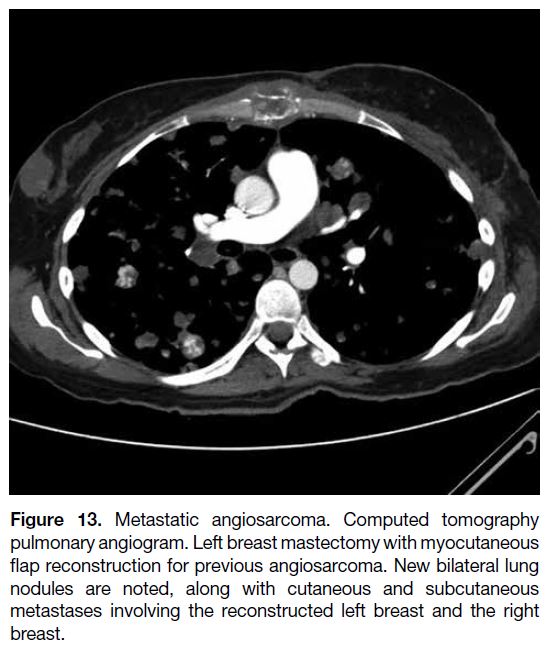

Angiosarcomas carry a poor prognosis, with the

majority of the cases in our centre showing disseminated

hypervascular metastases or contralateral breast

metastases despite radical surgery performed after

diagnosis (Figure 13).

Figure 13. Metastatic angiosarcoma. Computed tomography

pulmonary angiogram. Left breast mastectomy with myocutaneous

flap reconstruction for previous angiosarcoma. New bilateral lung

nodules are noted, along with cutaneous and subcutaneous

metastases involving the reconstructed left breast and the right

breast.